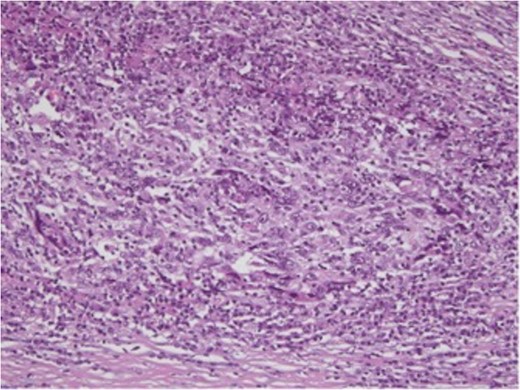

Microscopically, the hepatic lesion showed hepatocellular elements with solid and partly syncytial growth pattern. The nuclear atypies and mitotic figures were important (Fig. 5). A dense lymphoplasmatic infiltration prevalent in the periphery was found (Fig. 6). The immunohistochemical analysis showed membranous staining for β-catenin (Fig. 7). No immunoreactivity of tumor cells was detected for HerPar (Fig. 8), CK 7b (Fig. 9), AFP, S-100, EBV and EBER. Mismatch repair proteins (MMR) retained immunohistochemical staining. Immunohistochemistry for light Ig clearly showed that the plasma cells in the infiltrates were polyclonal. This configuration is typical of a medullary-like HCC.

H&E-stained slide, ×50. Large anaplastic cells with enlarged vesicular nuclei, prominent nucleoli and numerous mitoses.